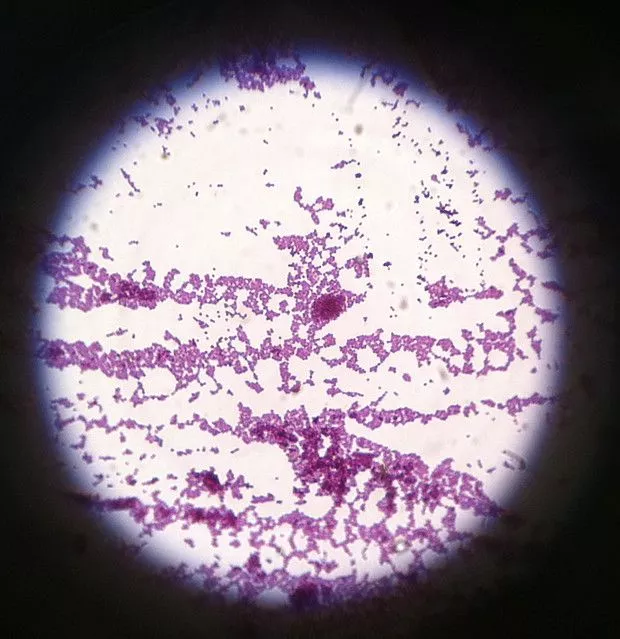

Gram Staining Result and Interpretation

- Gram-positive reaction– These cells appear blue or purple. It is the result of a thick peptidoglycan layer which retains the crystal violet–iodine complex during decolorization.

- Gram-negative reaction– These cells appear pink or red. The thin peptidoglycan and lipid-rich outer membrane allow the primary stain to escape, so the cells take the counterstain.

- Cell morphology– The smear is observed for cocci, bacilli, or coccobacilli. It is the step for understanding basic bacterial shape.

- Arrangement of cells– Clusters, chains, pairs, or tetrads is seen in Gram-positive cocci. Rods, curved rods, or diplococci is seen in Gram-negative bacteria.

Gram Staining Images